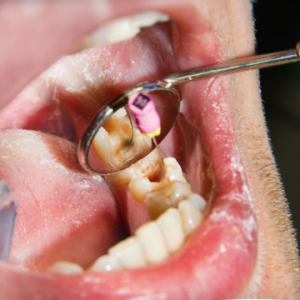

La instrumentación del conducto radicular se realiza mediante instrumentos de endodoncia, asistidos por sistemas de irrigación, en condiciones de trabajo asépticas. La instrumentación del canal...

Con sus irregularidades y complejidades anatómicas, el sistema de conductos radiculares es uno de los espacios clínicamente más difíciles de la...